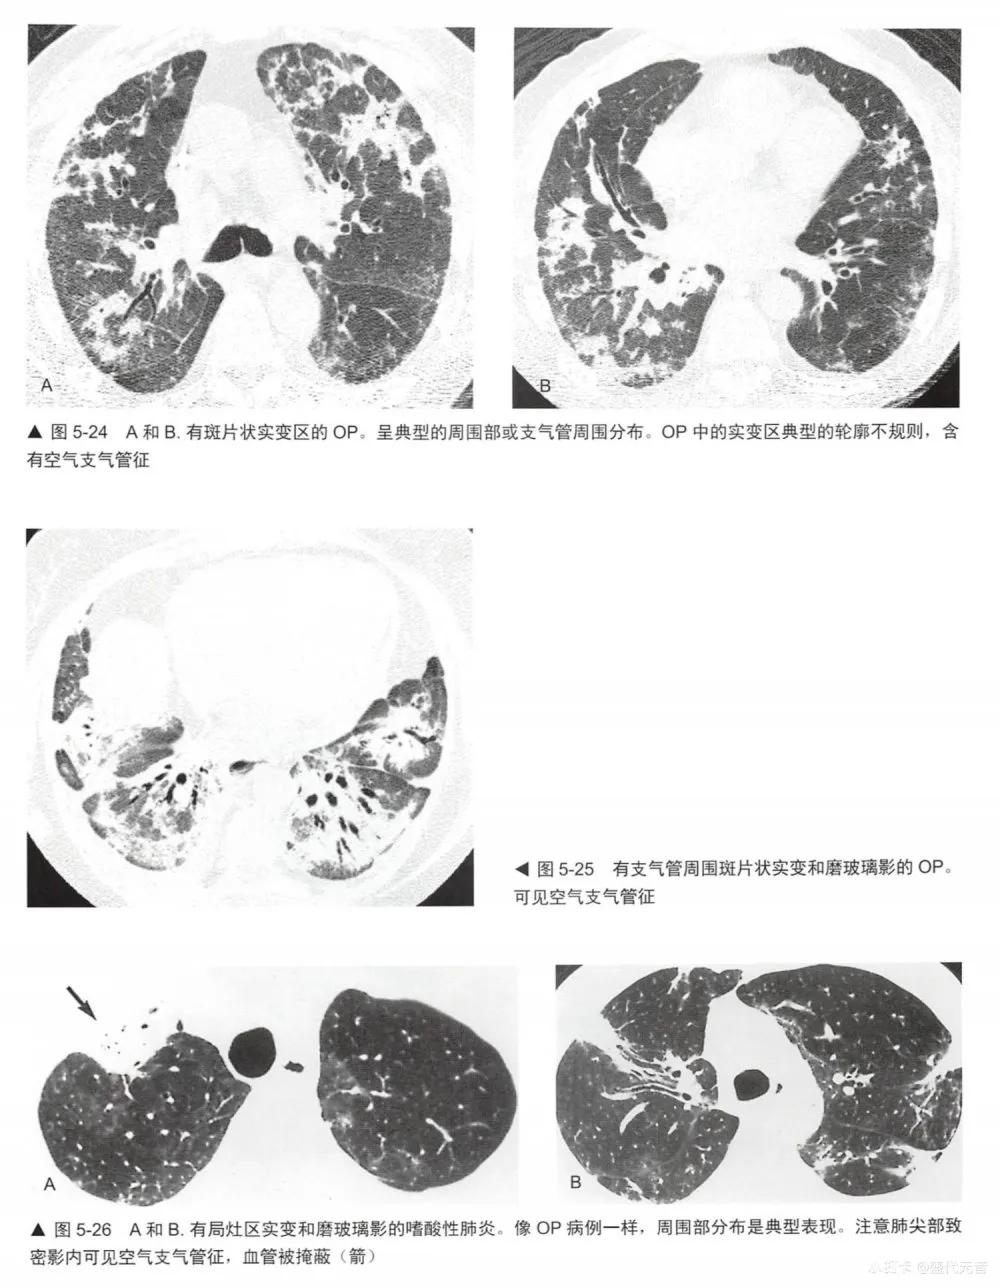

实变是指肺衰减增加并掩蔽了肺血管(图5-1,图5-24〜图5-28)可有空气支气管征(图5-28)。如胸片上已可见明确的实变证据时,HRCT对病例的诊断几乎无帮助。无论如何,HCRT可在胸片有诊断性之前检出实变。实变可伴有局灶性磨玻璃影和小叶中心性结节(图5-28,图5-29)。

实变的鉴别诊断与磨玻璃影(表5-1)有相当大的重叠,事实上,许多表5-1列出的疾病都显示为这两种表现的混合(表5-5)。实变的鉴别诊断包括不同原因的肺炎:最典型的是细菌性(图5-28),但也包括分枝杆菌、真菌性肺炎(图5-29)、支原体、耶氏孢子菌和病毒性肺炎; 0P (图5-24和图5-25);嗜酸性肺炎(图5-26,图5-27),如NSIP和DIP的间质性肺炎;HP (图5-30);放射性肺炎、浸润性黏液腺癌(图5-16和图5-31); LIP;淋巴瘤(图5-32)和淋巴增生性疾病;肺泡蛋白沉着症;结节病;药物反应,肺水肿和肺出血;AIP, DAD和ARDS。与吸入动、植物油脂或矿物油有关的外源性类脂性肺炎,可导致磨玻璃影或实变,此时因含有脂肪是低衰减的(图5-33)。